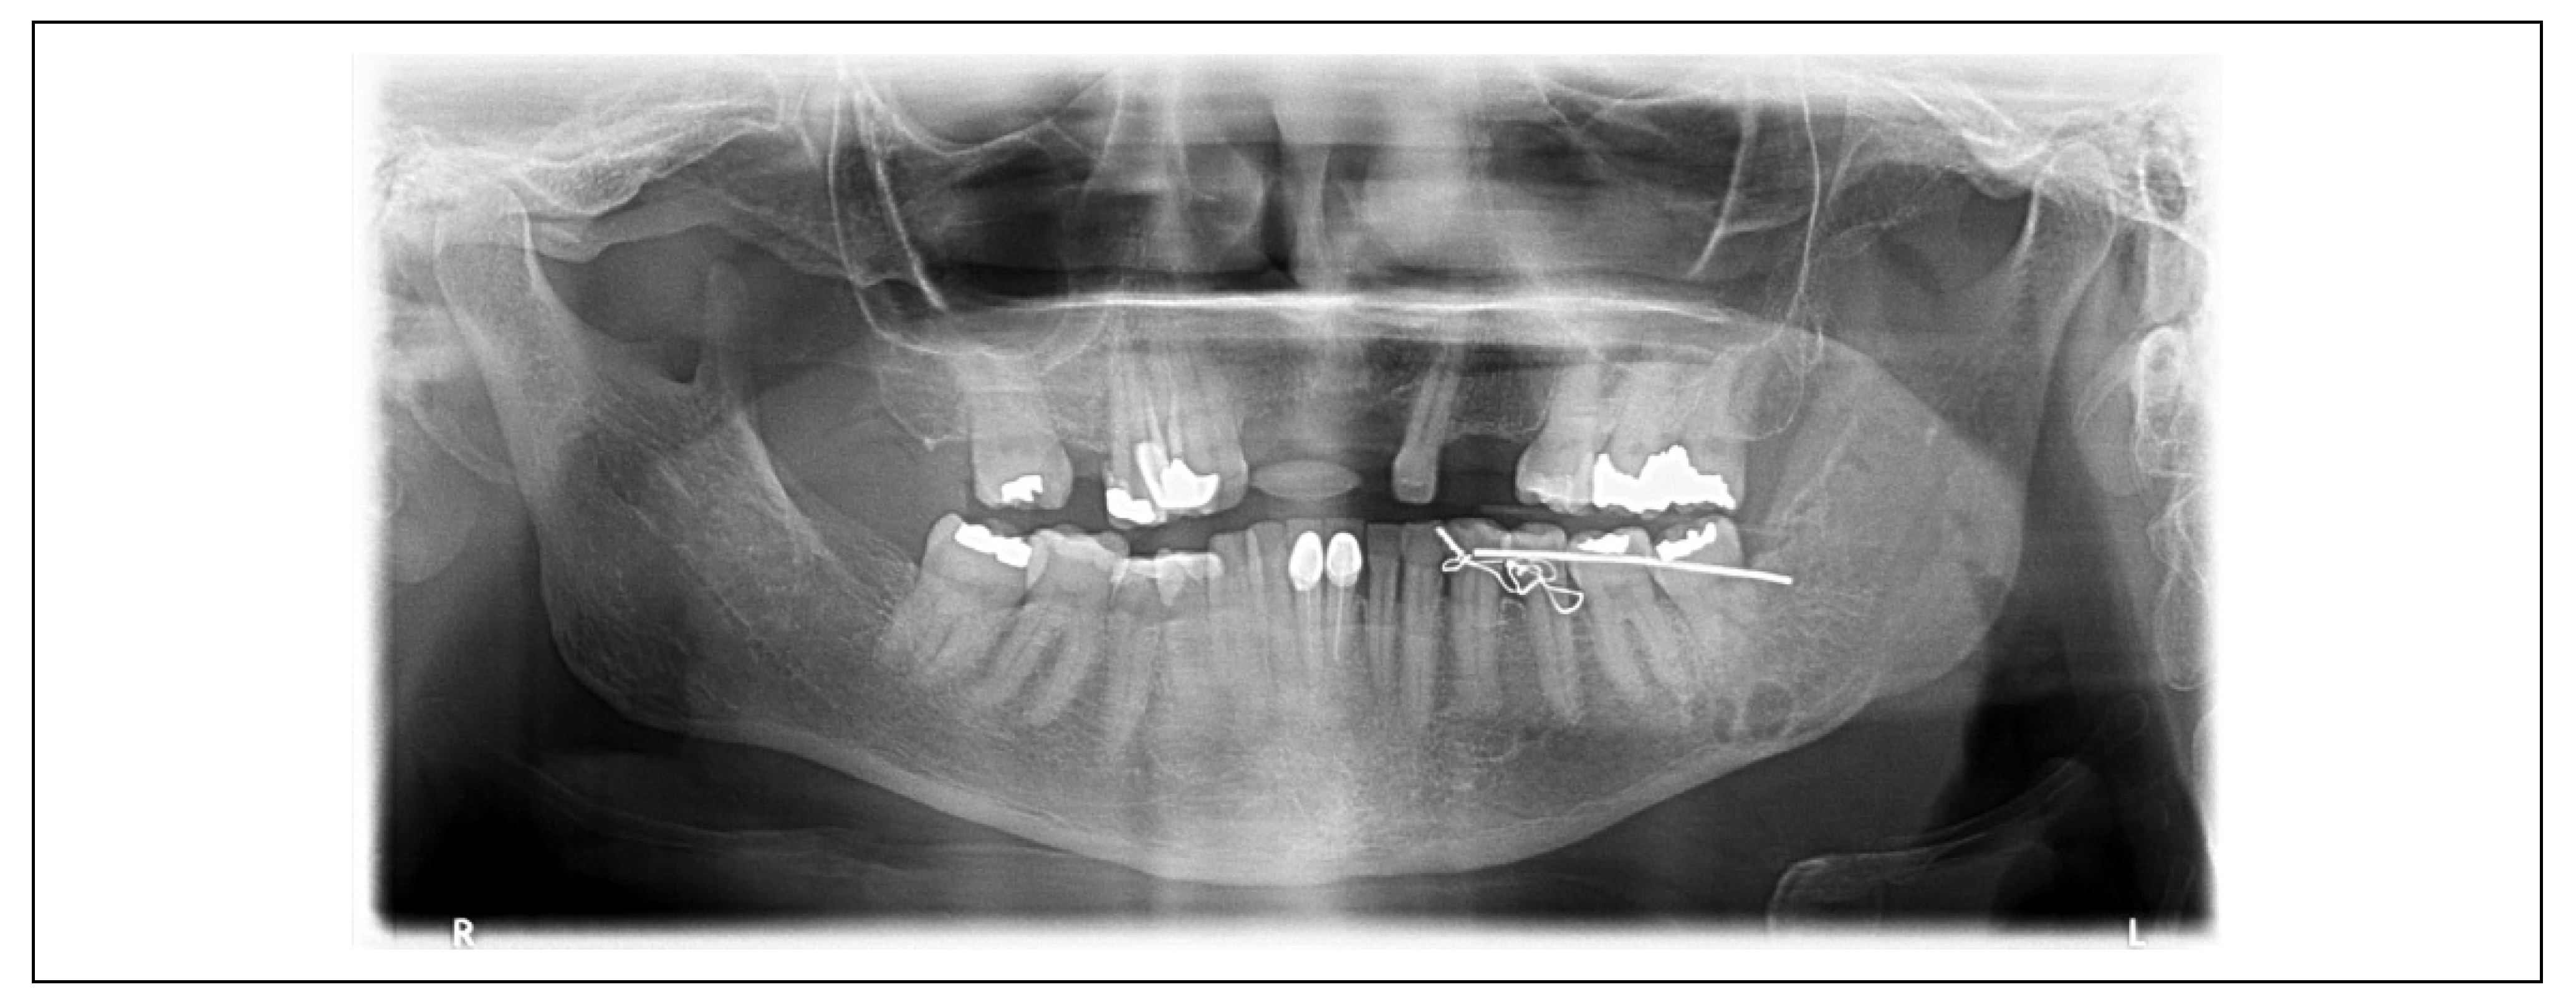

| 1 | 3.1 × 3.7 = 11.47 cm2 | 1.9 × 1.9 = 3.61 cm2 | 68.52% | Moderate reaction |

| 2 | 7.5 × 3.5 = 26.25 cm2 | 5.5 × 1.6 = 8.80 cm2 | 66.47% | Moderate reaction |

| 3 | 3.5 × 3.6 = 12.60 cm2 | 2.1 × 1.9 = 3.99 cm2 | 68.33% | Moderate reaction |

| 4 | 2.0 × 2.2 = 4.40 cm2 | 0.8 × 0.7 = 0.56 cm2 | 87.27% | Good reaction |

| 5 | 3.8 × 9.1 = 34.58 cm2 | 2.7 × 5.7 = 15.39 cm2 | 55.49% | Moderate reaction |

| 6 | 4.2 × 4.7 = 19.74 cm2 | 0.7 × 0.7 = 0.49 cm2 | 97.51% | Good reaction |

| Total | 18.17 cm2 | 5.47 cm2 | 73.93% | Moderate reaction |